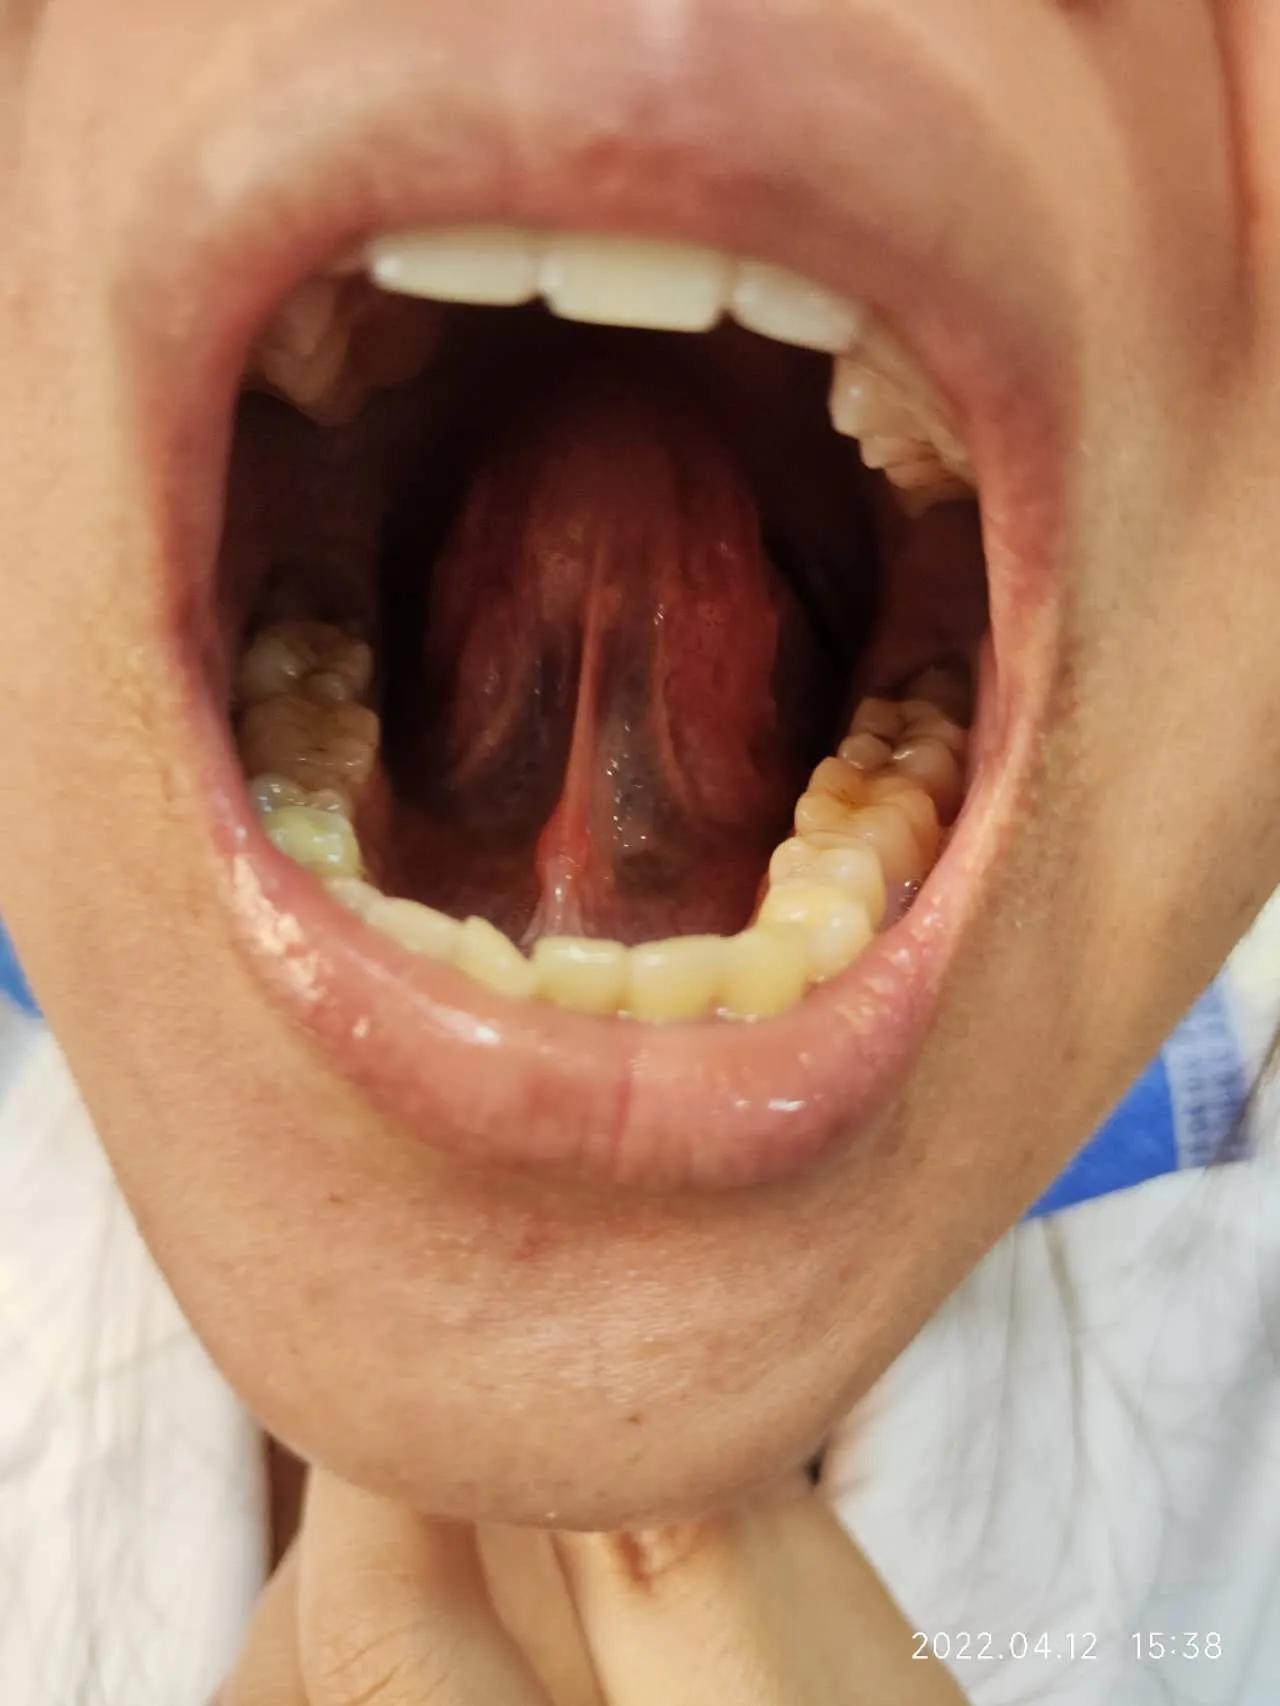

服药前

服药后